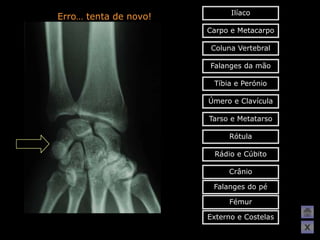

Erro… tenta de novo!

Ilíaco Erro… tenta denovo! Carpo e Metacarpo Coluna Vertebral Falanges da mão Tíbia e Perónio Úmero e Clavícula Tarso e Metatarso Rótula Rádio e Cúbito Crânio Falanges do pé Fémur Externo e Costelas X